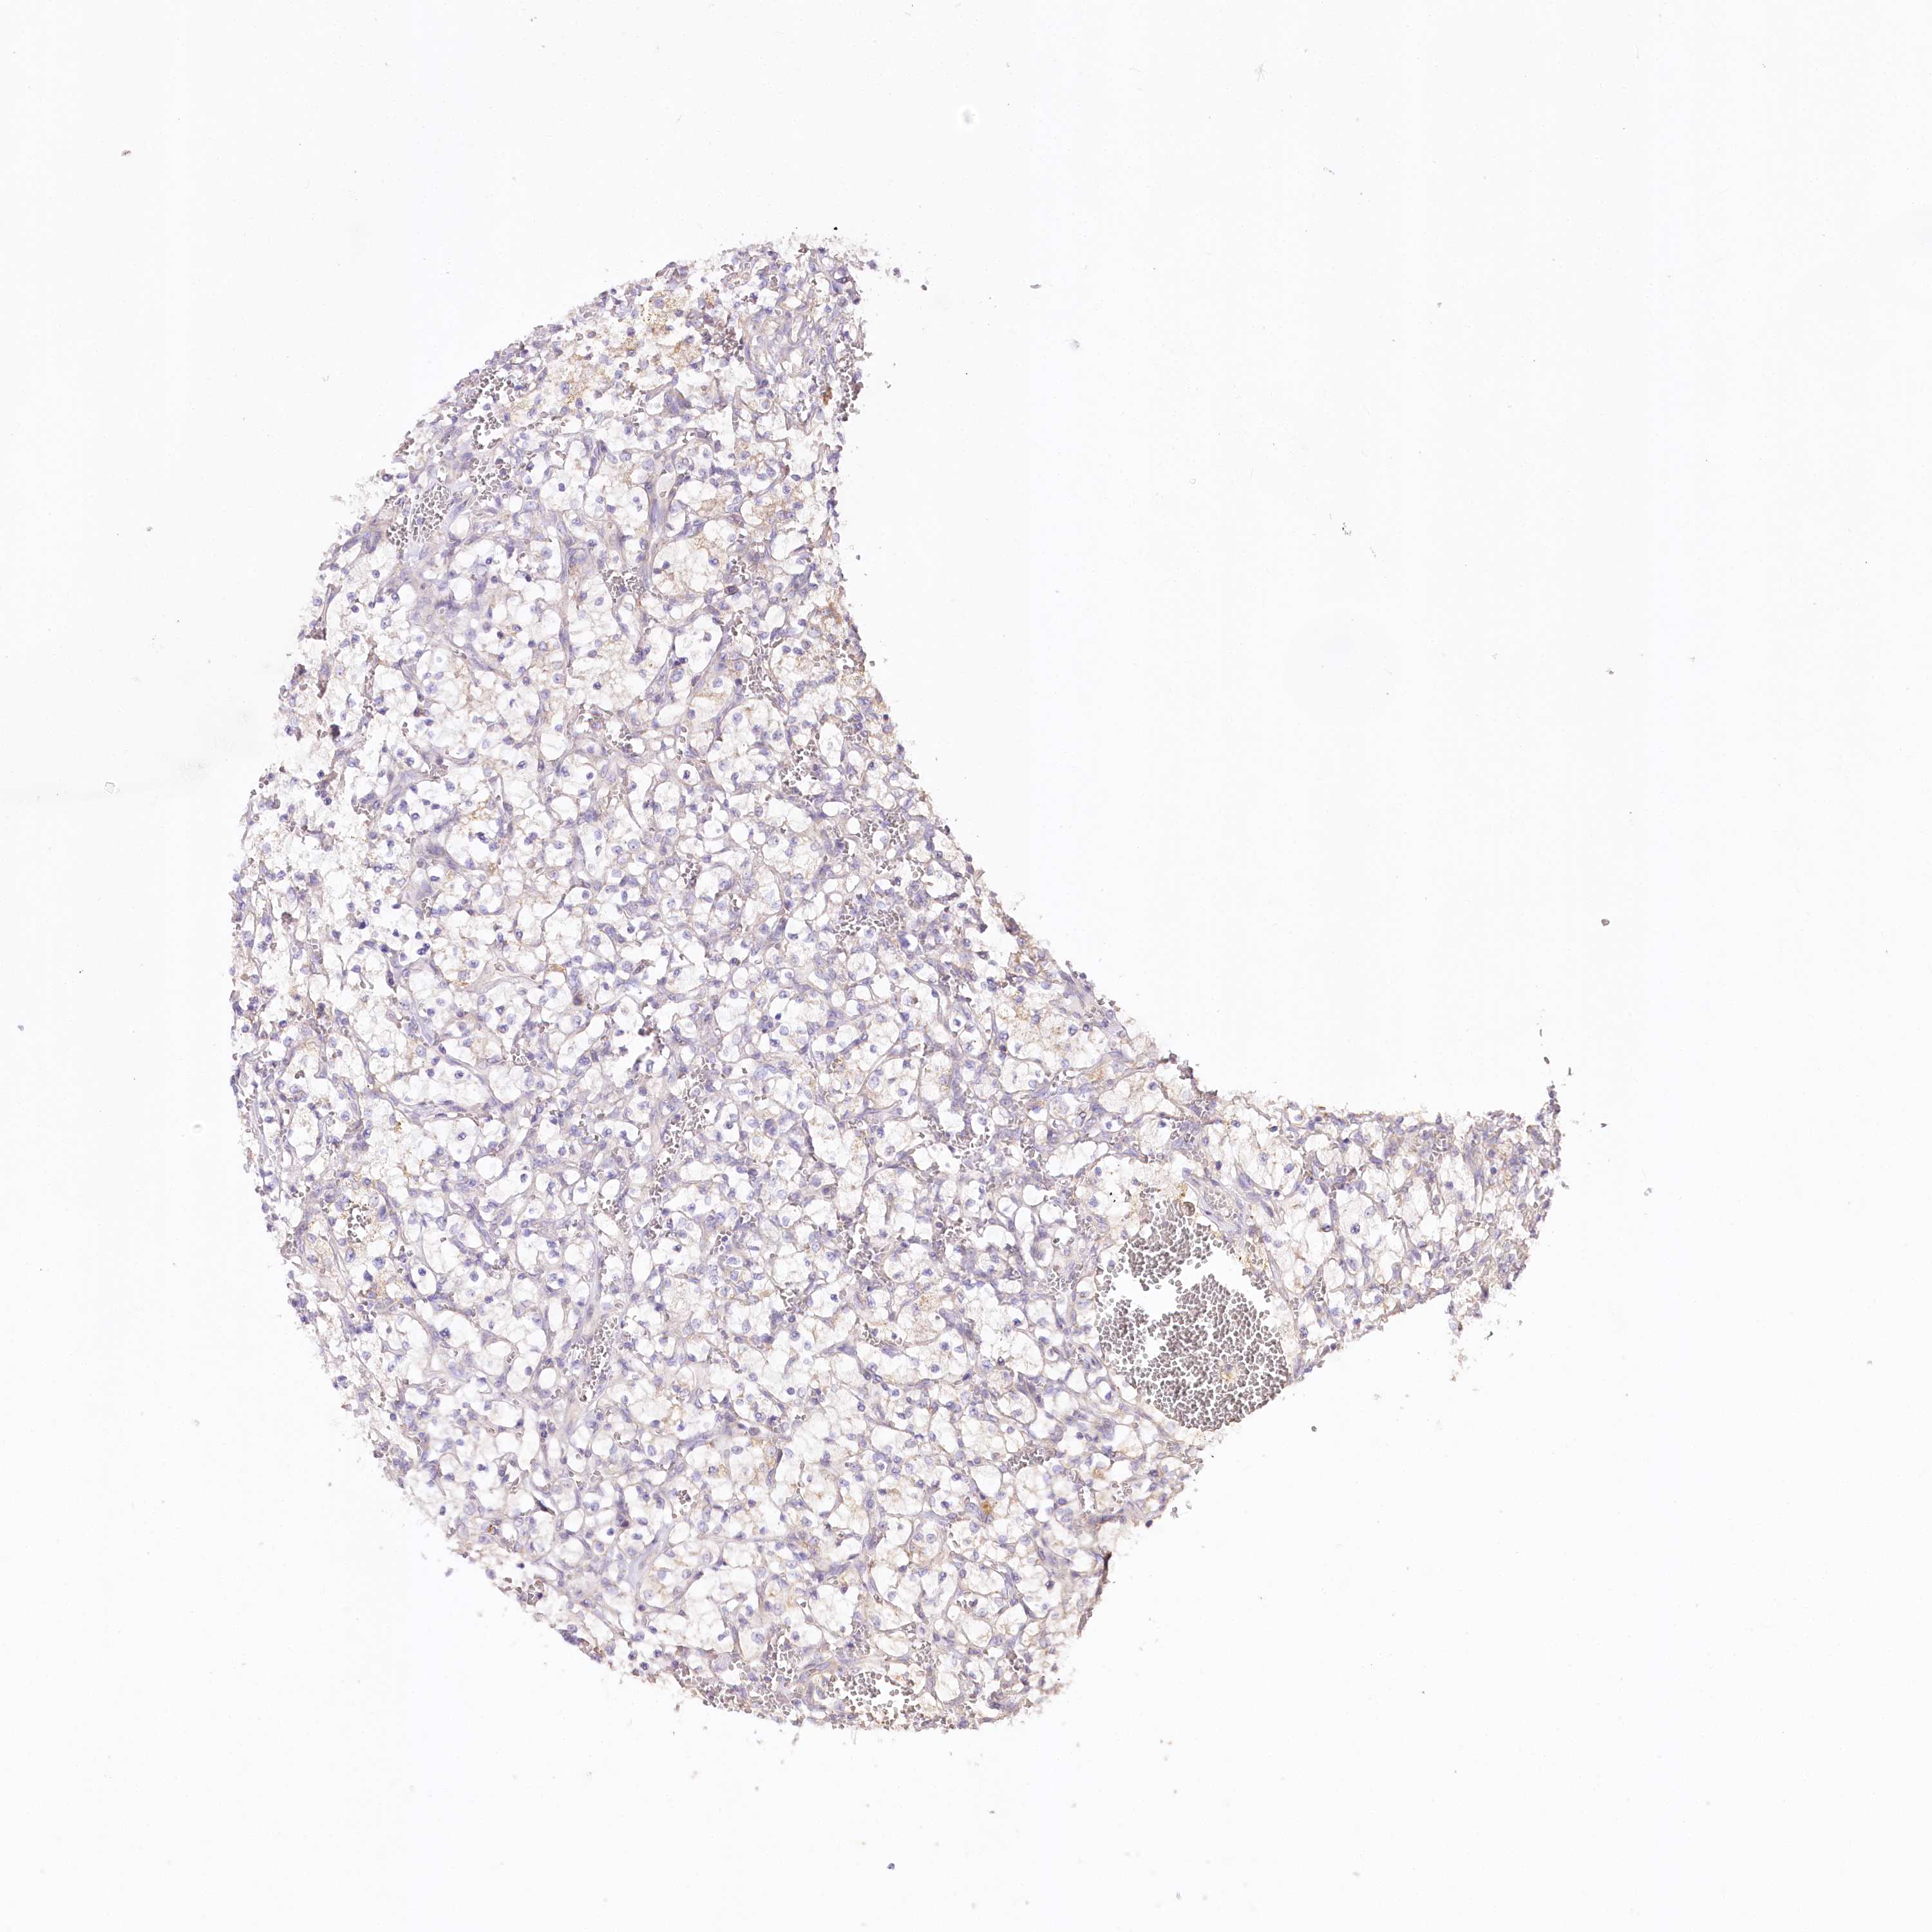

KIDNEY RENAL CLEAR CELL CARCINOMA (TCGA) - Interactive survival scatter ploti

The Survival Scatter plot shows the clinical status (i.e. dead or alive) for all individuals in the patient cohort, based on the same data that underlies the corresponding Kaplan-Meier plots. Patients that are alive at last time for follow-up are shown in blue and patients who have died during the study are shown in red.

The x-axis shows the expression levels (FPKM) of the investigated gene in the tumor tissue at the time of diagnosis. The y-axis shows the follow-up time after diagnosis (years). Both axes are complimented with kernel density curves demonstrating the data density over the axes. The top density plot shows the expression levels (FPKM) distribution among dead (red) and alive patients (blue). The right density plot shows the data density of the survived years of dead patients with high and low expression levels respectively, stratified using the cutoff indicated by the vertical dashed line through the Survival Scatter plot. This cutoff is automatically defined based on the FPKM cutoff that minimizes the p-score. The cutoff can be changed by dragging the vertical line or by entering a cutoff value in the square labeled "Current cut-off".

Under the Survival Scatter plot the p-score landscape (black curve; left axis) is shown together with dead median separation (red curve; right axis). Dead median separation is the difference in median mRNA expression between patients who have died with high and low expression, respectively. It is calculated as follows: median FPKM expression of dead patients with high expression - median FPKM expression of dead patients with low expression. This is intended to aid the user in visually exploring custom cutoffs and the associated p-scores and dead median separation.

Individual patient data is displayed and can be filtered by clicking on one or more of the category buttons on the top of the page. Categories describing expression level and patient information include: high, low, alive, dead, female, male and tumor stages. The scale of the x-axis can be toggled between linear and log-scale by clicking on the "x log" button. Mouse-over function shows TCGA ID, patient information and mRNA expression (FPKM) for each patient.

& Survival analysisi

Kaplan-Meier plots summarize results from analysis of correlation between mRNA expression level and patient survival. Patients were divided based on level of expression into one of the two groups "low" (under cut off) or "high" (over cut off). X-axis shows time for survival (years) and y-axis shows the probability of survival, where 1.0 corresponds to 100 percent.

ZNF226 is not prognostic in Kidney Renal Clear Cell Carcinoma (TCGA)